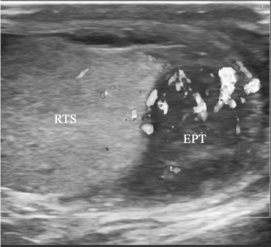

图31-7 附睾炎声像图(见彩图41)

附睾尾部增大,回声低,CDFI:内血流较丰富